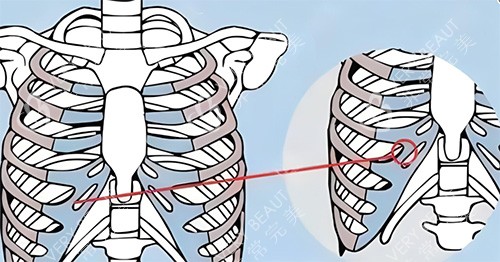

当时,医生跟我介绍说,用自己的肋骨隆鼻,材料取自自身,不会有排异反应,结果也会很自然。我心动不已,毫不犹豫地就做了手术。

我赶紧去医院询问医生,医生告诉我,这是肋骨鼻吸收的正常现象。原来,肋骨在植入鼻子后,会有一定程度的吸收,每个人的吸收情况不同,我的吸收情况相对明显一些。